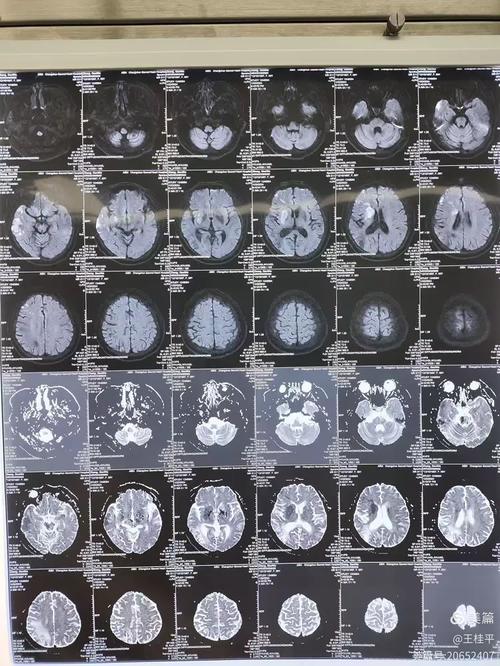

- 立即复查MRI:这是最关键的步骤,如果高度怀疑但CT正常,医生会立刻安排头部MRI检查,特别是DWI序列,以明确是否存在早期梗死。

- MRI是早期脑梗死的“火眼金睛”,对于怀疑脑梗但CT正常的患者,应尽快进行头部MRI检查以明确诊断。

- CT的局限性:CT主要看的是密度变化,对于早期细胞级别的缺血不敏感,而磁共振成像,特别是DWI序列(弥散加权成像),对早期脑缺血(发病后几分钟到几小时)就非常敏感,被称为诊断早期脑梗死的“金标准”。